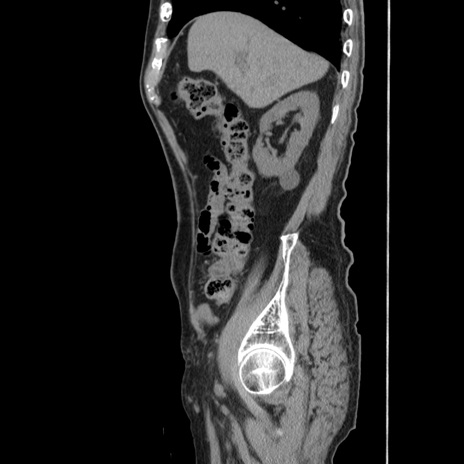

症例24(矢状断像)

【症例】80歳代男性

【主訴】左側腹部痛、嘔吐

【現病歴】本日早朝より左腹部に痛みあり。昼頃嘔吐認めたため、救急要請。

【既往歴】直腸癌(Mile手術)、胆摘

【身体所見】意識清明、BT 35.9℃、BP 221/93mmHg、SpO2 97%(RA) 、腹部:左ストーマ周囲に限局性の腹部膨隆あり。 膨隆部自発痛・圧痛あり・軟。

【データ】WBC 7700、CRP 0.09